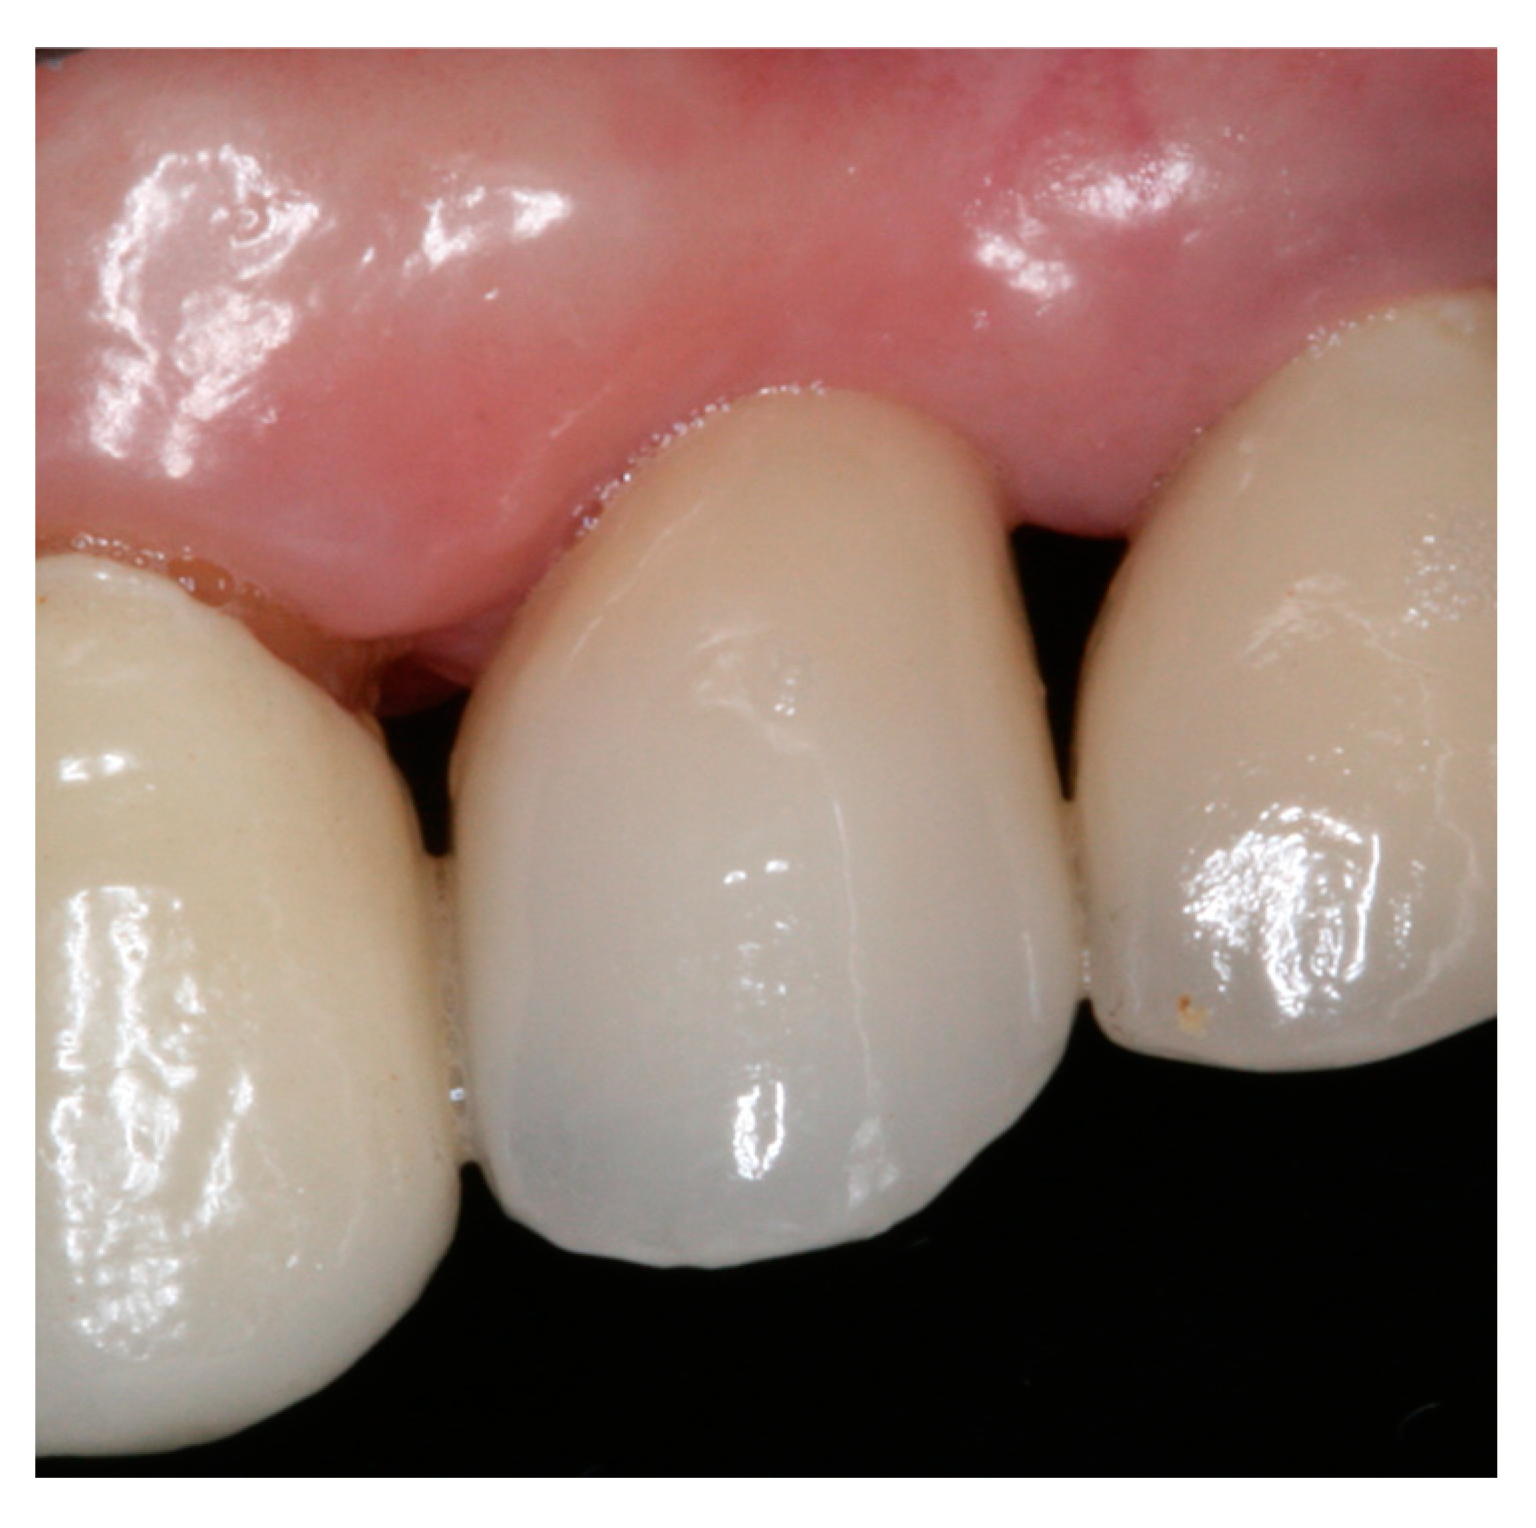

2. Materials and Methods

3. Results